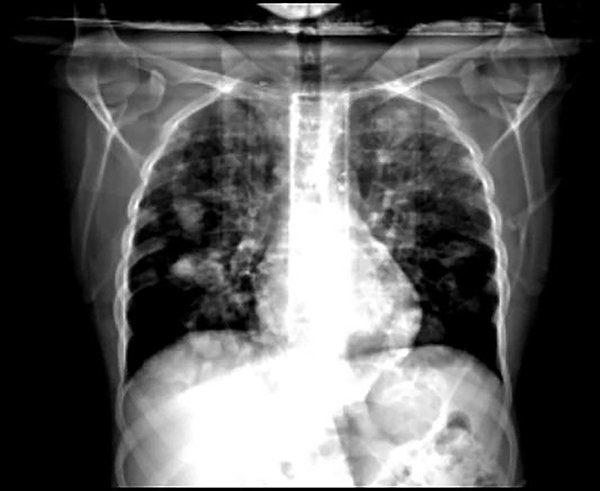

La TC de tórax mostraba múltiples nódulos pulmonares de variado tamaño, los dominantes promediaron los 35 mm y se localizaban en los segmentos anteriores del LSI y LID y en el segmento externo LII (fig. 3). Derrame pleural bilateral laminar. Ecografía testicular izquierda: formación sólida, heterogénea, de aproximadamente 9 x 7,5 cm, que presentaba señal de flujo ante la evaluación en modo Doppler color y desplazaba las estructuras adyacentes. Tales hallazgos sugieren proceso atípico primario.

Figura 3. TC de tórax: múltiples nódulos pulmonares con derrame pleural bilateral.